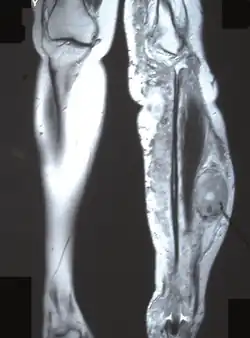

MRI (coronal plane) showing the site of MPNST in the left tibia.